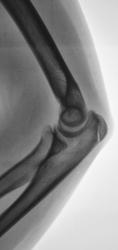

Пациент (подросток) направлен хирургом в рентгеновский какбинет для рентгенографии локтевого сустава. Накануне - травма. Произведено исследование. Ваше мнение коллеги по поводу наличия или отсутствия перелома.

Малышка – Иринка, правоту которой я предполагаю, предположила апофизеолиз локтевого отростка, а его, на мой взгляд, можно определить лишь в боковой проекции.

Конечно, Петрович - Вы правы. Формально можно предположить апофизеолиз локтевого отростка, с учетом неравномерности ширины "зоны росткового хряща". Но из-за болевого синдрома, классическую "строго боковую" лаборантам произвести не удалось.

А апофизеолиза локтевоо отростка здесь нет? Зона роста неравномерная, резко сужена в верхнем отделе.

Здесь не хватает боковой проекции здоровой руки. Больная же в боковой проекции снята вполне удовлетворительно.